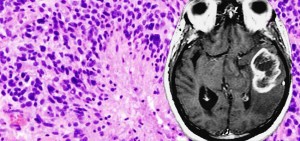

13+ Brain Tumor Survivor Stories Glioblastoma Multiforme PNG. Www.braintumor.org > your voice > share your story on november 28th, 2015, my father was diagnosed with glioblastoma multiforme stage four brain cancer. Glioblastoma multiforme (gbm) is the most common and aggressive type of primary brain tumor.

Glioblastoma also known as glioblastoma multiforme or with the acronym gbm is the most common and most aggressive among brain cancers. Bill asenjo, a survivor of six brain tumor surgeries, is completing his phd dissertation (alternative medicine and disability) at the university of iowa. The changed or abnormal cells often grow to form a. So the idea with this video is to tell.